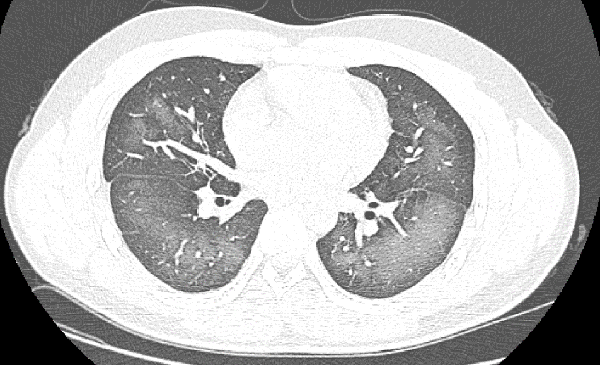

??? ?? ? CT ???? ??? ?? ?? ???? ?? ??? ??? ???? ‘??’?? ?????.

‘??’? ????? X? ?? CT ???? ?? ??? ??? ???? ??? ?? ?? ????, ???? ? ?? ??????? ???? ???? ?? ??? ???.

?????????? ??? ??? ? ?? ?????????? ?? ? ??? ?? ?? ???? ?? ‘??’? ?? ?? ?? ??? ??, ???? ?? ?? ????? ???? ?? ???? ?? ??? ??? ? ??? ???.

? ?? ??? ???? ???? ??????? ??? ?? ????? ‘??’? ????. ????? ????, ????, ??? ? ?? ??? ? ? ??? ??? ?? ?????.